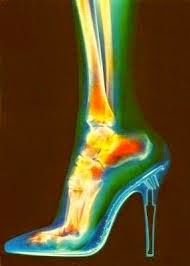

Vi racconto una storia bizzarra, ma non troppo, anzi è una quelle storie riguardanti alla realtà lavorativa del nostro paese. Premessa necessaria: lavoravo presso una cooperativa sociale come lavoratrice dipendente con la mansione di educatrice con contratto indeterminato. Il giorno di Pasqua pochi minuti prima di iniziare il mio turno di lavoro sono scivolata per le scale di casa e ritenendo il mio malessere poco serio mi sono recata sul posto di lavoro, lavorando per tutto il turno. Il dolore al piede era accentuato ma non pensavo si trattasse di una frattura, per farla breve mi sono fratturata il metatarso e ho dovuto inserire placca e chiodi. Ora ho un piede bionico per prendere a calci chi voglio!